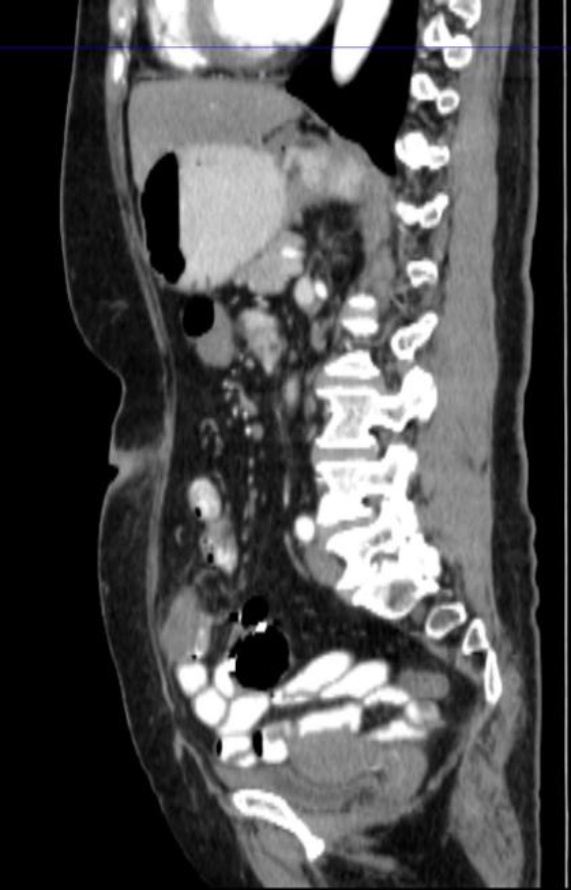

出院后患者为行扩大根治手术,来我院就诊。给进一步完善相关检查,腹部增强CT示:

患者阑尾未见明确显示,相应区短条状高密度影,周围条片及淋巴结影,边欠清,部分轻度强化征象,局部肠壁模糊,右下腹肠系膜及大网膜条片影,边欠清。区段小肠肠壁明显增厚,考虑肿瘤可能性大(见图4(a)图4(b))。经多学科讨论后,考虑患者阑尾肿瘤合并小肠肿瘤可能性大,各项术前检查未见明显转移征象,建议再次行手术探查。术中见:肝周及盆底血性积液,量约100 ml,部分小肠黏连与腹壁原切口下方,顿性分离黏连肠管,部分小肠、大网膜黏连固定于右下腹回盲部,松解黏连后,见回盲部、临近小肠系膜、大网膜及右侧腹壁触及质硬结节,距回盲部2 m处小肠肠管明显增粗、质硬,肝脏表面光滑,无明显占位。给予切除距回盲部远端10 cm升结肠及近端10 cm回肠,行回肠及升结肠吻合。切除距回盲部2 m处病变小肠,行小肠吻合。术后病理示:(距回盲部2 m处小肠):黏液癌(隆起型,3 × 2 cm),肿瘤侵透浆膜,脉管癌栓(−),神经侵犯(+),两侧手术切缘未见癌累及,肠周淋巴结内未见癌转移(0/2) (见图5图6)。(回盲部小肠):送检小肠组织,黏膜慢性炎,浆膜面及肠系膜内出血、纤维组织及间皮增生并见少许无上皮黏液,两侧切缘未见癌累及,肠周淋巴结内未见癌转移(0/10)。病理分期:pT4bN0Mx。(右半结肠)送检肠管组织,浆膜面见少量异型腺体浸润,意见为癌。周围组织呈异物肉芽肿性炎,两侧手术切缘未见癌累及,肠周淋巴结内未见癌转移(0/21)。(腹膜结节)送检组织内纤维组织结节状增生。(大网膜)网膜组织内见多处纤维组织增生伴异物巨细胞反应。经多学科会诊讨论后,考虑患者诊断原发肿瘤来自小肠,阑尾肿瘤为小肠侵犯所致。术后患者于肿瘤科行3周期Xelox方案化疗:奥沙利铂130 mg/m2,静脉输注2 h,第1天。卡培他滨每次1000 mg/m2,每日2次,第1~14天。患者术后随访至今未见异常。

(a) (b)

Figure 4. Abdominal CT (Before the second surgery)

4. 腹部CT(第二次手术前)